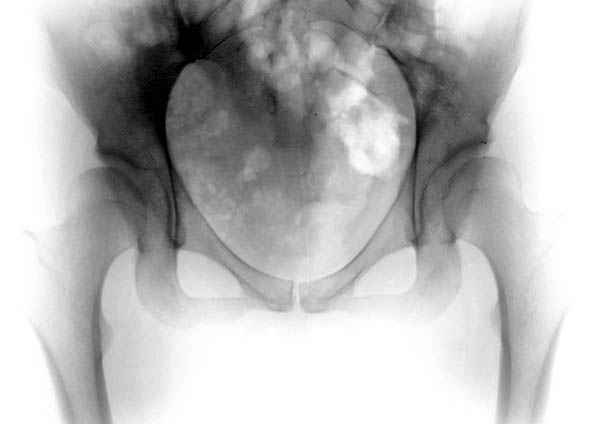

Картина типичной эволюции дисплазии сустава "кистовидная перестройка", на фоне неправильного взаймоотношения сустава "да тут угол Виберга 0 градусов" на вершине наибольшей нагрузки в вертлужной впадине образовался участок разрежения, "киста", в последующем через этот участок образуется перелом - стадия фрагментация дисплазии.

Для установки диагноза достаточно информации, на рентгенограмме передний и задний край ацетабулум образовали перекрест, "цифру восемь", указывающий на небольшую ретроверсию, а суставная щель одинаковой ширины на всем протяжении, что доказывает, что с покрытием хряща проблем нет. Головка бедра покрыта всего наполовину, это явное нарушения взаимоотношений.

А для данного случая, необходим прямой снимок таза с отдельными суставами, также включить боковые снимки сустава, немаловажно знание покрытия головки спереди.